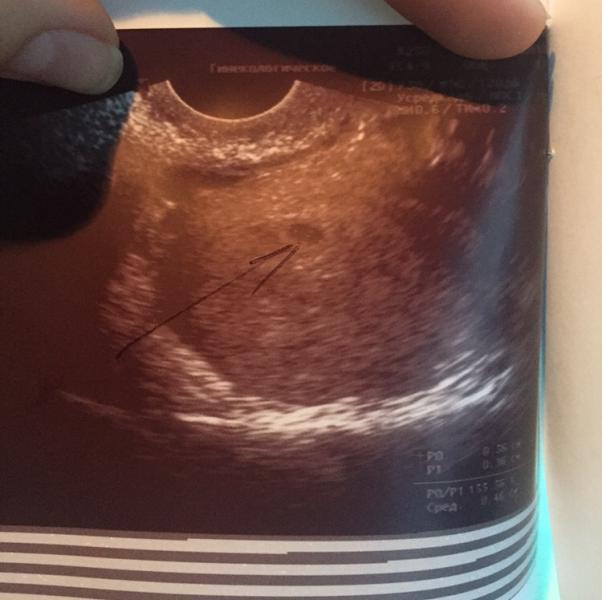

Ровно год назад, 19 июня, мы узнали что будем родителями самой замечательной крошки на свете, с тех пор мы безмерно счастливы!! На фото нашей горошинке 5 недель! 🐣